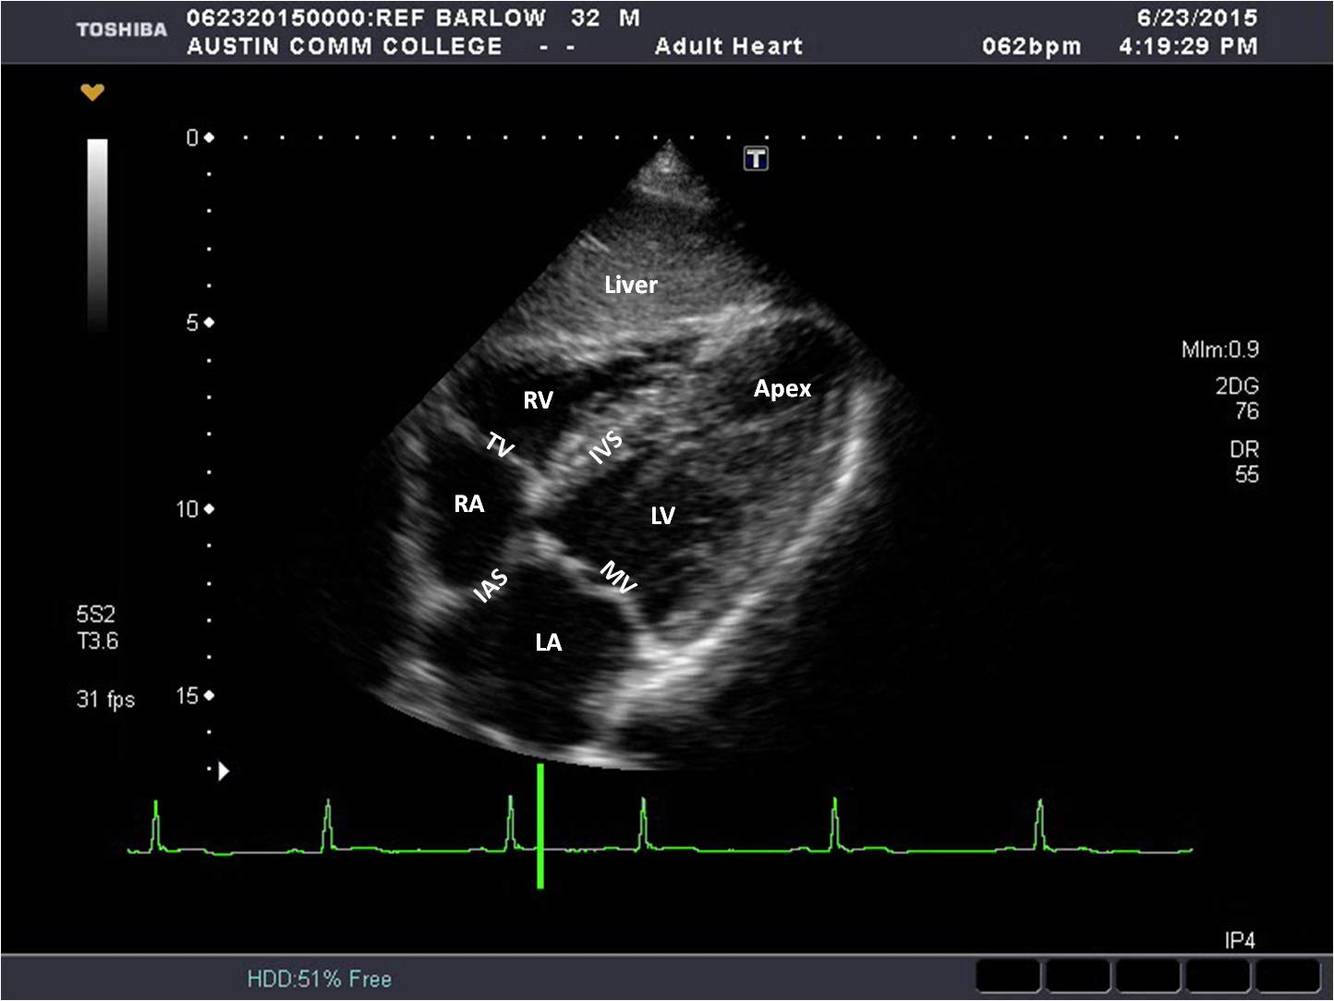

Name the view

apical four chamber